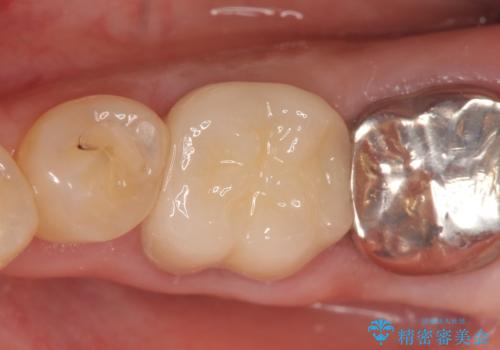

再根管治療終了後、オールセラミッククラウンによる補綴を行いました。

今回用いたオールセラミッククラウンはジルコニアフレームという白い素材の上にセラミックを盛っているため、審美性が非常に高いのが特徴です。

また、ジルコニアは人工ダイヤモンドの材料にも使われているほど高い強度を持っており、そのためオールセラミッククラウンは審美性だけでなく、奥歯やブリッジの補綴も可能とするクラウンです。